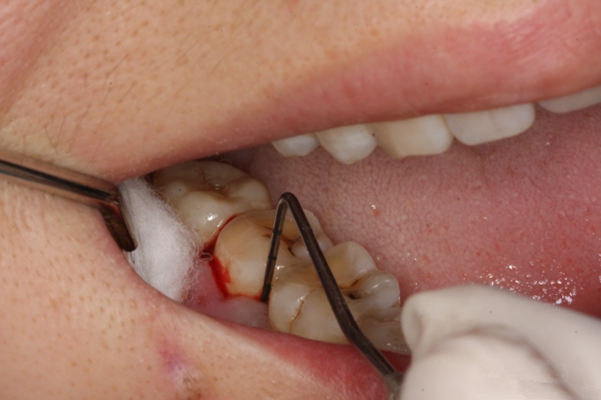

牙周袋 (48)